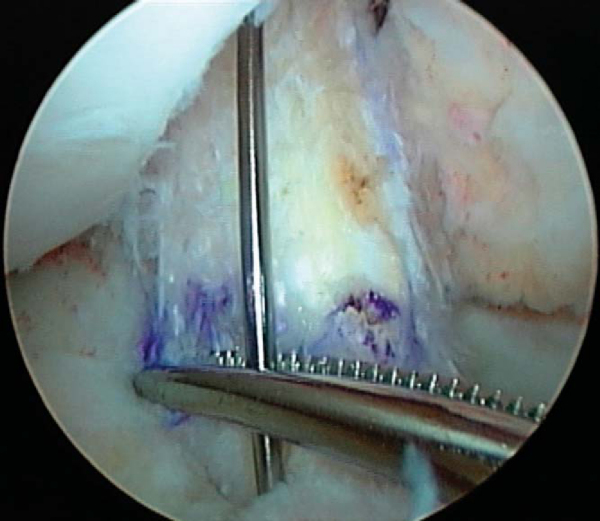

For tibial side fixation, I prefer a polylactate bioabsorbable screw, 5 to 10 mm from the joint space (near but not at the tunnel opening into the joint). On the basis of studies by Nagarkatti,[8] we use a PLLA screw one size larger than the tibial tunnel size and place it carefully through the tibial tunnel, over a guide pin (

Fig. 63-8

), while holding the knee at 20 degrees of flexion and at tension equivalent to a 30- to 40-pound pull after thoroughly cycling the graft after femoral fixation. We are sure to insert the screw by turning (not pushing) the screw so that there is no risk of pushing the graft back. We prefer two sets of No. 5 whipstitches (FiberWire is a desirable alternative) coming off the tibial end of the graft (four strands). Although it is not necessary to achieve a stable knee, these suture ends may be tied over a button at the tunnel entrance for added security.